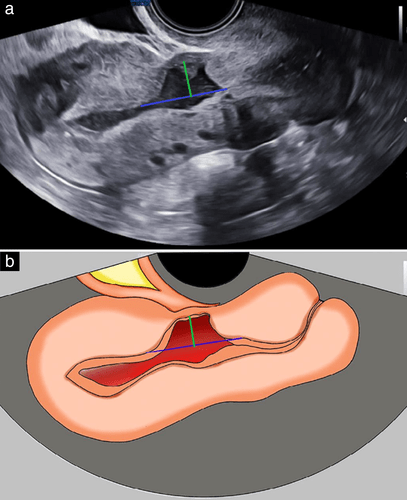

„Niche” to z angielskiego „nisza”, „wnęka”. Słowo to dość obrazowo oddaje problem. Objaw niche pojawia się bowiem w opisach blizny po cesarskim cięciu w badaniu USG. Jest to ubytek tkanki w bliźnie, jaka powstała w mięśniówce macicy. Niche obserwowany jest w dolnym odcinku trzonu macicy, czyli miejscu połączenia trzonu i szyjki macicy.

Według Bij de Vaate i współpracowników możemy mówić o objawie niche, kiedy ubytek tkanki wynosi 1mm w badaniu USG. Van der Voet i współpracownicy mówią o 2 mm.

Rycina pochodzi z artykułu „How to perform standardized sonographic examination of uterine niche in non-pregnant women” pod redakcją C. Verberkt. Ultrasound in Obstet & Gyne, Volume: 60, Issue: 3, Pages: 420-424, First published: 24 May 2022, DOI: (10.1002/uog.24953)